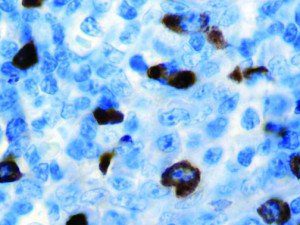

It is the ICU physician who is most likely to witness one of the deadliest manifestations of the abnormal immunological response, the cytokine storm syndrome (CSS). This response is also referred to by some as the cytokine release syndrome (CRS). CSS is characterized by continuous activation and expansion of macrophage and lymphocyte populations, which secrete large amounts of cytokines, causing the cytokine storm. This massive cytokine release is akin to hemophagocytic lymphohistiocytosis (HLH) disease, a syndrome characterized by initial unchecked and persistent activation of cytotoxic T lymphocytes and NK cells.

Clinical and laboratory manifestations of HLH include fever, enlarged liver and/or spleen, neurologic dysfunction, coagulopathy, liver dysfunction, cytopenias (i.e., low levels of erythrocytes, leukocytes, and/or platelets), hypertriglyceridemia, hyperferritinemia, hemophagocytosis, and eventually diminished NK cell activity as the immune system becomes progressively paralyzed. HLH can be familial (primary HLH) or secondary to another disease process (sHLH), such as rheumatic disease, in which it is referred to as macrophage activation syndrome (MAS, characterized by elevated ferritin).